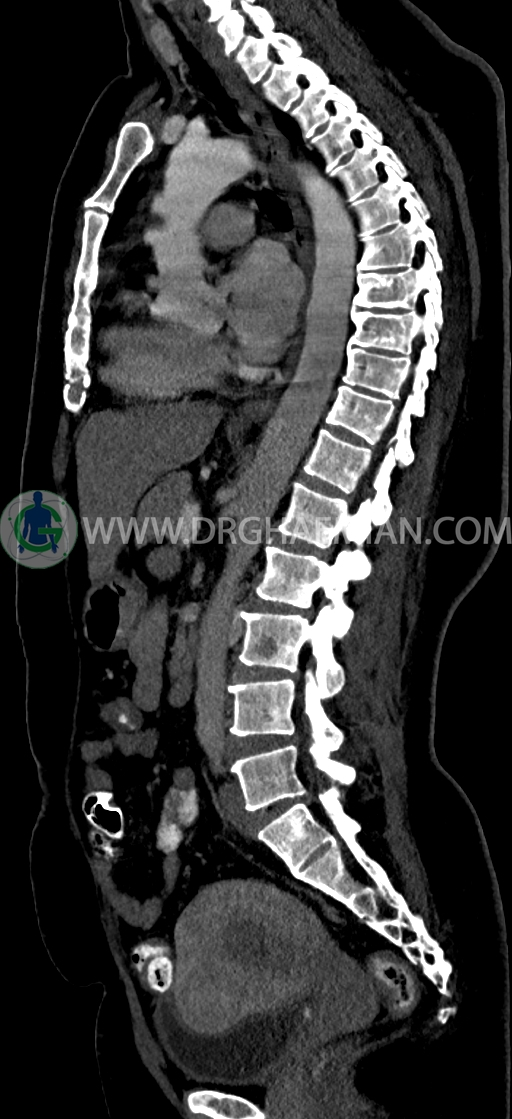

سی تی اسکن شکم و لگن یکی از روش های تصویربرداری با سی تی اسکن است. این روش با استفاده از اشعات ایکس تصاویر عرضی از ناحیه شکمی و لگنی ایجاد میکند. در این کیس سی تی اسکن هیپراستوز اسکلتی ایدیوپاتیک منتشر (DISH)، فیبروم اینترامورال، هرنی سوپرا امیلیکال دیده می شود.

در سي تي اسکن اسپيرال ريه و مدياستن-شکم و لگن با کنتراست خوراکی و وريدی (مولتي ديدکتور 16 با مقاطع ظريف و بازسازي هاي ساژيتال و کرونال) :

–Bridging osteophyte در مهره هاي توراسيک مطرح کننده DISH همراه با کيفوز مشهود است.

–lumbosacral transitional vertebrae